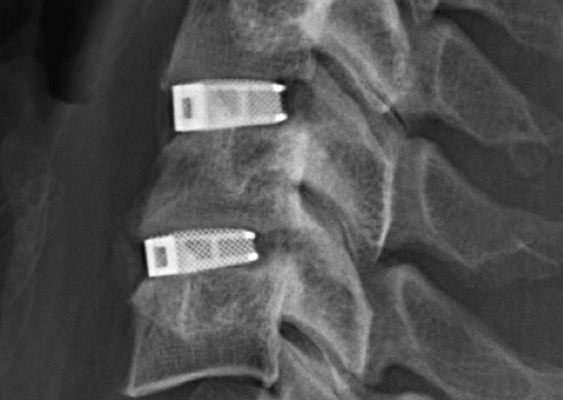

Клинический пример. Пациентка К., 39 лет, обратилась с рецидивом болевого синдрома после выполненной 6 мес назад микрохирургической интерляминэктомии на уровне LV—SI, удаления грыжи диска. По данным магнитно-резонансной томографии выявлены рецидив грыжи диска без миграции фрагмента в краниальном и каудальном направлениях, снижение высоты диска на 75% от исходной, что в совокупности с остеофитами вызывало компрессию корешка LV справа. С учетом необходимости восстановить высоту диска с заданным углом принято решение о целесообразности тотальной дискэктомии из забрюшинного доступа с межтеловым эндопротезированием. Угол операционного действия составил 15°. Несмотря на столь небольшой угол операционного действия, рана длинной 83 мм и глубиной 94 мм при угле наклона оси операционного действия в 78° позволили без затруднений технически выполнить декомпрессию дурального мешка и нервных корешков. Длительность операции составила 92 мин, кровопотеря — 20 мл.

Решение поставленных задач у данной пациентки из дорзального доступа имело бы сложности из-за рубцового процесса по ходу доступа и в канале, а также сопровождалось неизбежным кровотечением из эпидуральных вен, что повлекло бы увеличение длительности операции и большую кровопотерю.